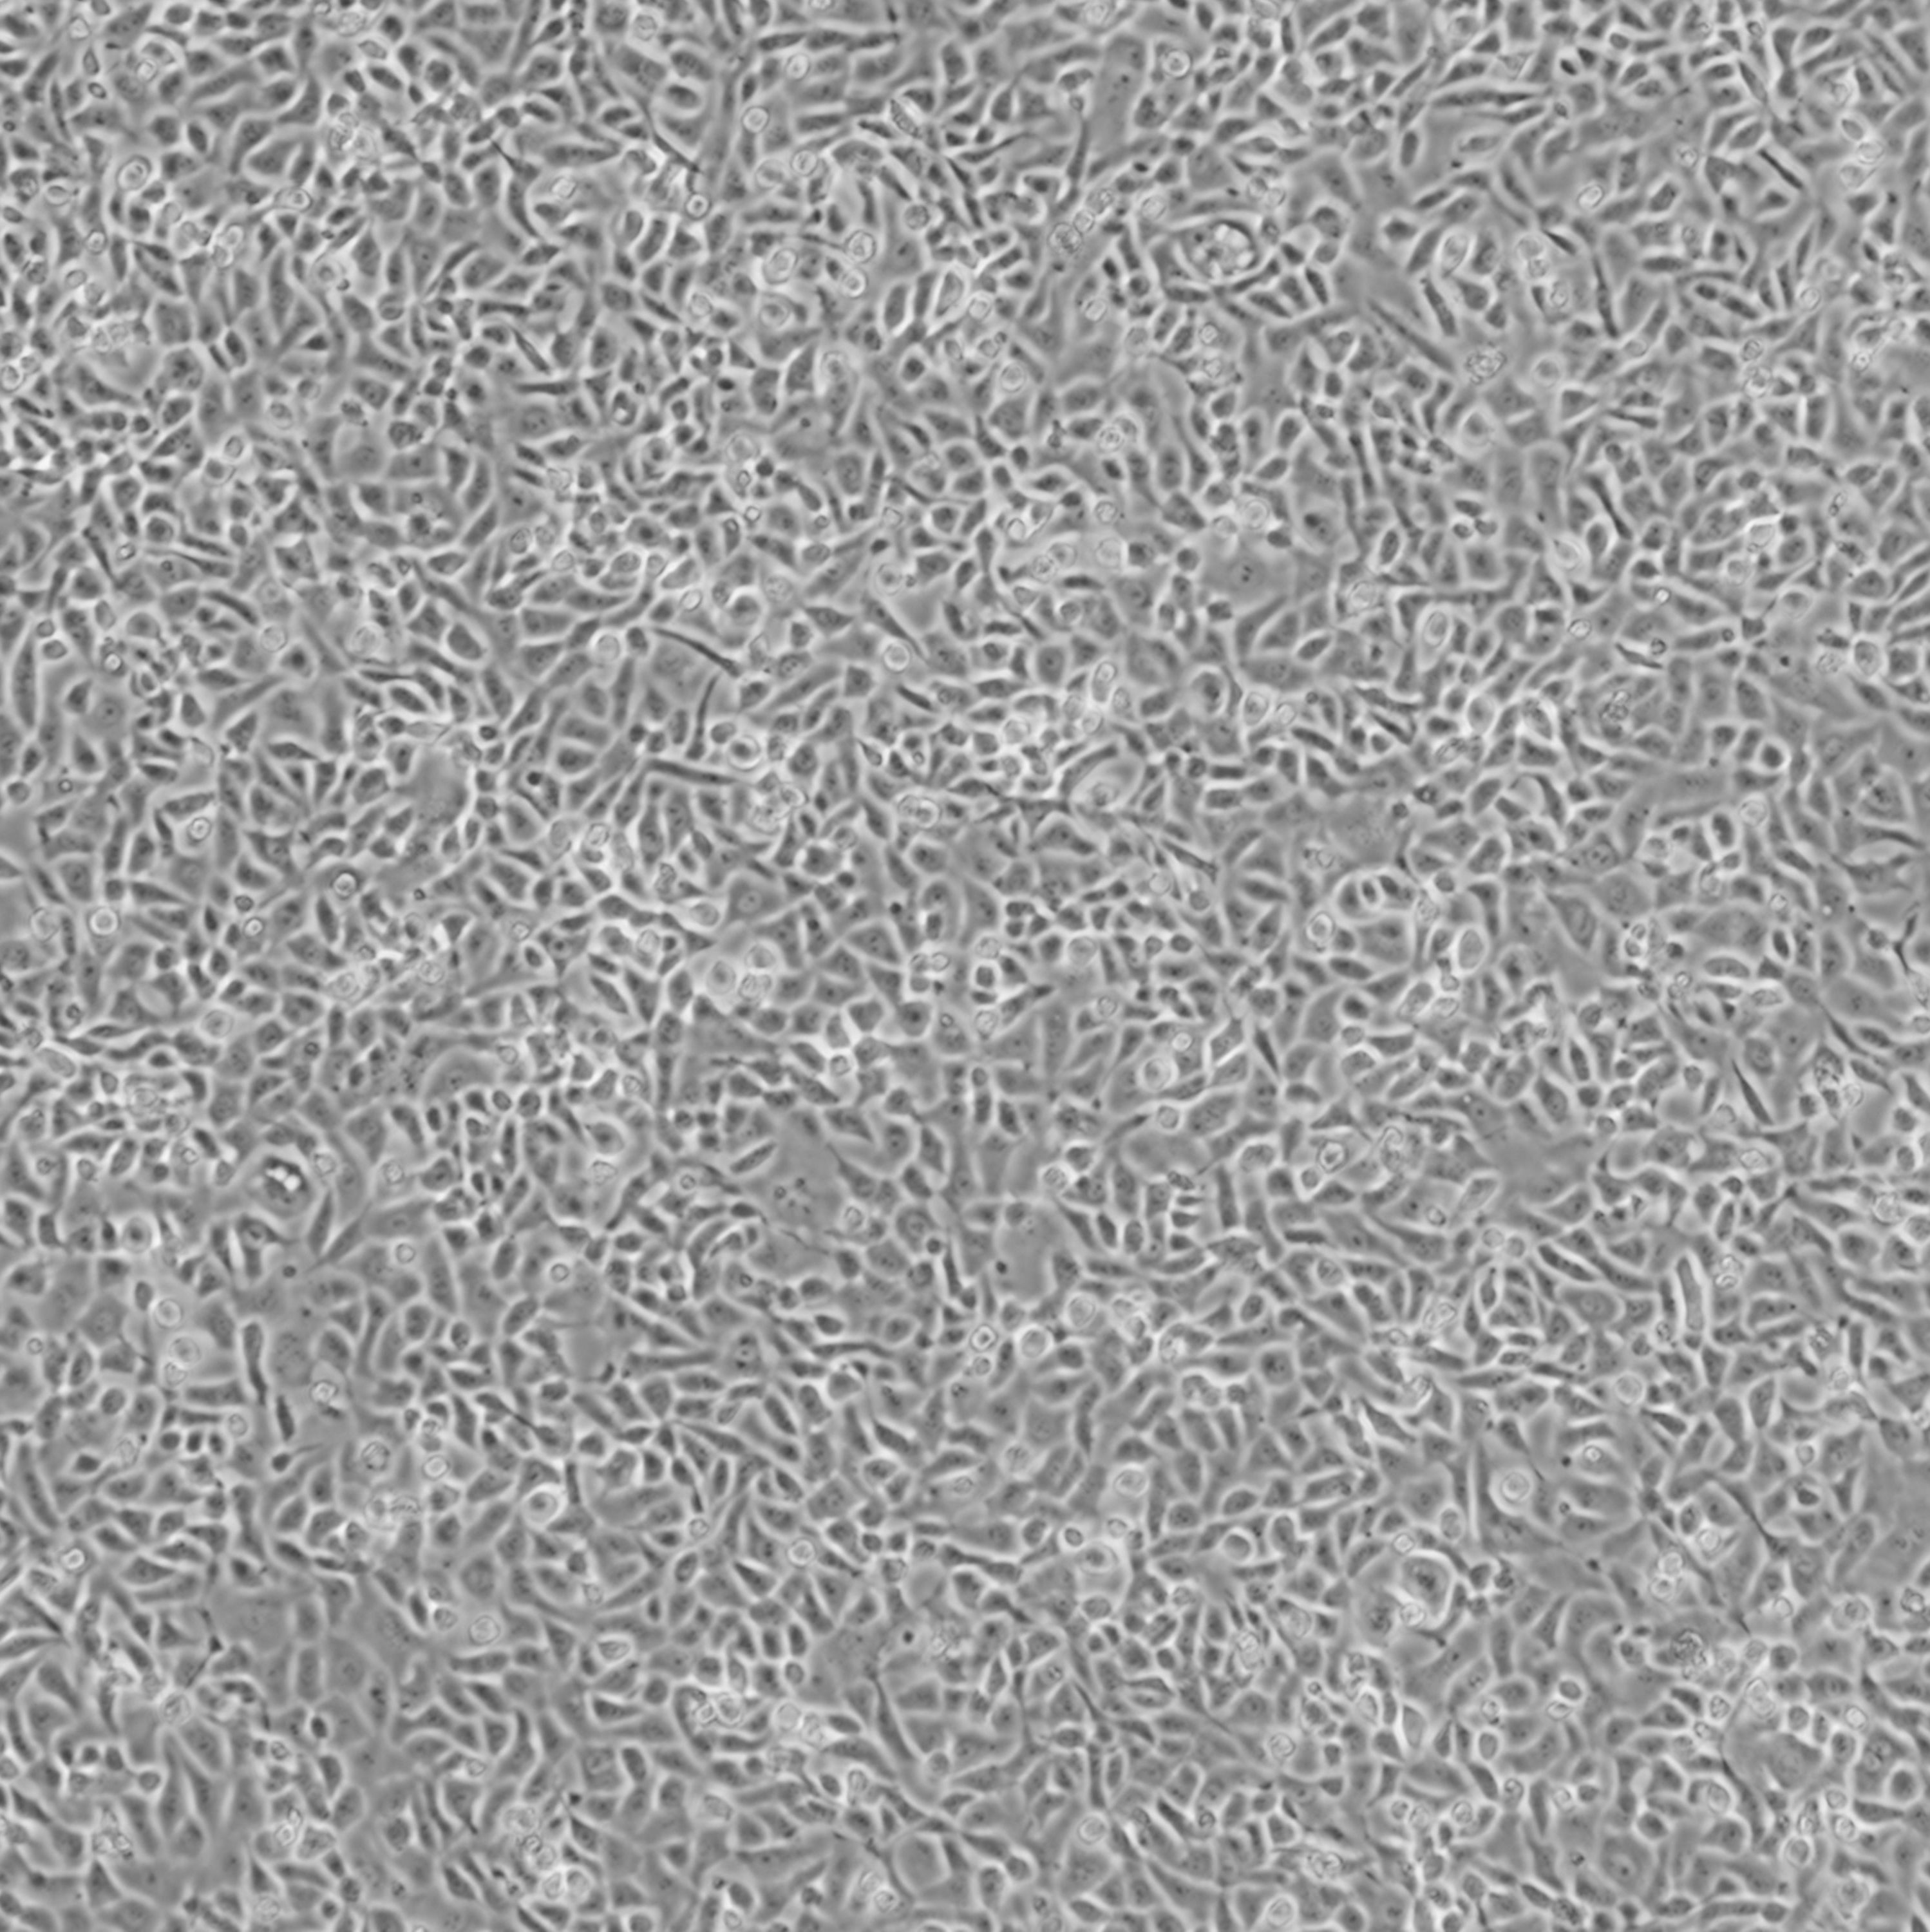

TYK-nu_人卵巢癌细胞

细胞名称:TYK-nu_人卵巢癌细胞

种属来源:人

性别年龄:女性,38岁

组织来源:卵巢

生长特性:贴壁生长

细胞形态:上皮样

细胞规格:1 X 106cells/T25或1 mL冻存管

培养条件:Eagle's minimal essential medium with 10% fetal calf serum

37 ℃, 5% CO2

文献和实验;(B)绿色荧光蛋白(GFP)标记的TYK-nu与T细胞共培养,E:T比为5:1,有或没有H2-scDb在Incucyte®系统中连续监测,显示24小时和96小时拍摄的相位和绿色荧光图像。 研究人员基于 CRISPR 的技术对携带内源性 HLA-A*02:01 和 p53R175H 的 KMS26、KLE 和 TYK-nu 癌细胞系中的 TP53 进行了基因破坏。H2-scDb 介导的细胞毒性通过破坏这些细胞中的 TP53 类似地减轻,通过Incucyte® 连续检测超过120h,呈现动态的定量

靶向 TP53 突变和 CD3 的双特异性单链抗体(scDb)。 研究人员首先确证了 p53R175H 在三种人肿瘤细胞系(KMS26, TYK-nu, KLE)中表达,并以 p53R175H/HLA-A*02:01 复合物的形式被呈递到细胞表面。通过噬菌体文库技术筛选得到了两个特异性靶向 p53R175H/HLA-A*02:01 复合物的抗体克隆,分别命名为 H2-scDb 和 H20-scDb。这两个克隆可以特异性地与 p53R175H/HLA-A*02:01 复合物结合,并激活 T 细胞